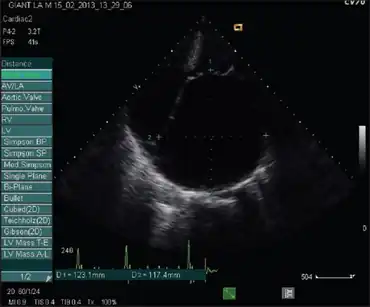

| Echocardiogram showing massive left atrial enlargement | |